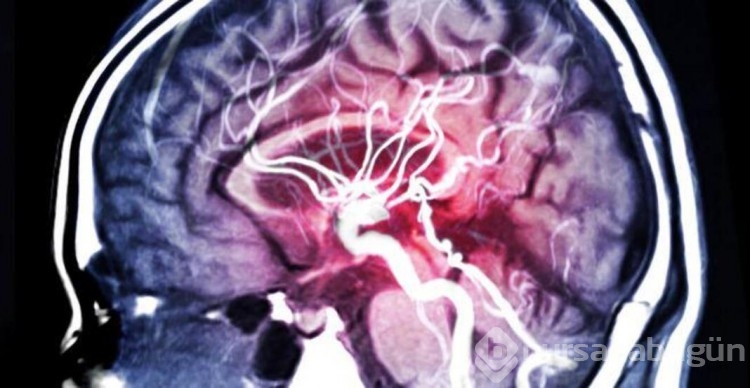

Unutkanlığı azaltan, zeka gelişimini tetikleyen yiyecekler yeni bir listede bir araya getirildi.Rehber niteliği taşıyan bu listeyi buzdolabının kapağına asmakta fayda var. İnsan her durumda yaratıcı düşünmeye, zihnini daha çok geliştirmeye ve beynini güçlendirmeye mecbur. İster şu yeni hızlanan bahar döneminde derslerle boğuşalım, isterseniz de iş yerinde 'ses getirecek' bir projeyle uğraşalım. 'Zihin açıklığı' dileklerine ne kadar ihtiyacımız varsa, zihnimize iyi bakacak yiyeceklere de en az o kadar ihtiyacımız var. İşte sizlere bin tane sudoku çözmüş gibi zekayı geliştiren yiyecek listesi...